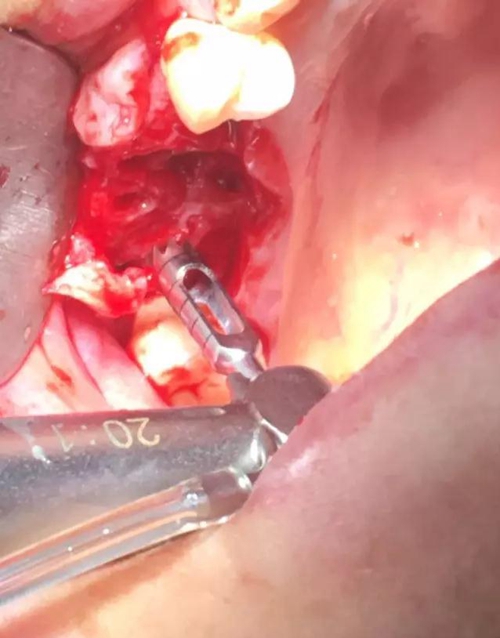

【病例分享】內(nèi)提,用自體骨柱,不用骨粉

1.jpg